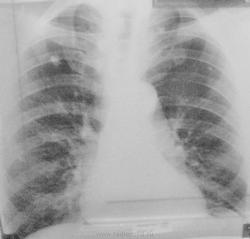

Помогите разобраться. Сегодня поступил мужчина 61год, температура 38 в течение двух недель, больше жалоб нет. Бледный очень ( анализы в работе). Заболевания отрицает, в контакте с тбс не был. Что тут может быть? Заранее извиняюсь за качество снимков...не было с собой фотика и негатоскопа:((((((

Я бы снял прицельную заднюю проекцию левой верхушки, т.к. за тенью первого ребра слева похоже туберкулома с распадом.Не выкашливает ли ваш дядя палочку из неё????

Старый туберкулезник с "застойными" легкими. И я доснял бы еще правый бок.

Больше данных за тбц, похоже там еще и в левом легком очаг ( инфильтрат ), отправьте к фтизиатрам.